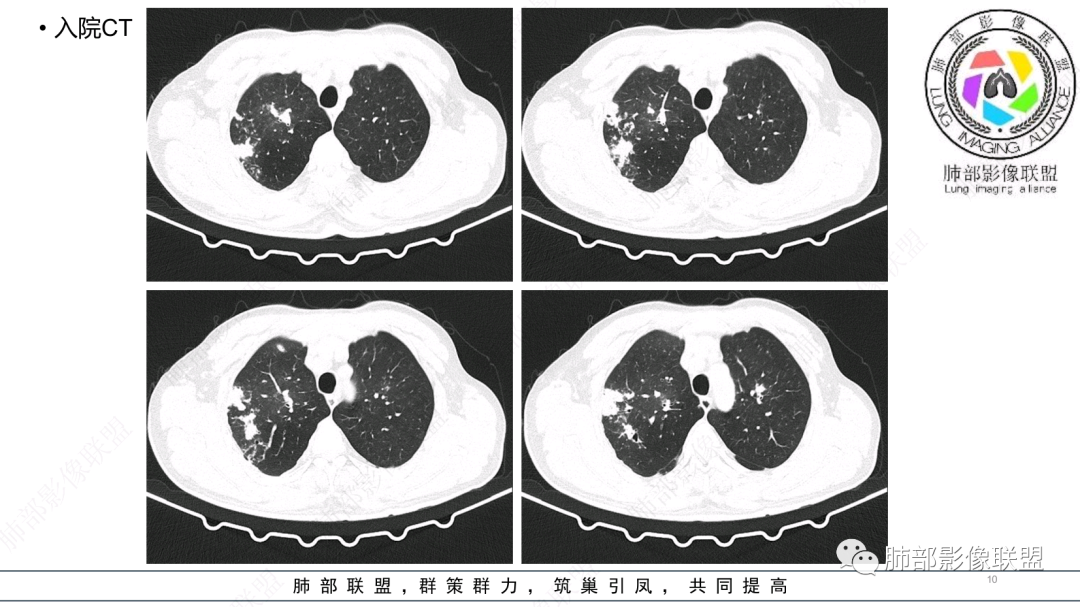

中老年男性,发病一周,发热,炎症指标明显增高,双肺支气管扩张基础,双肺可见多发结节、斑片状、团块状密度增高,边缘尚清。病灶分布与支气管关系密切,考虑支扩合并感染,铜绿,NTM、奴卡、曲霉等,环卫工人,可能接触腐败物较多,考虑曲霉可能大,鉴别奴卡。

中老年男性,发病一周,发热,炎性指标高,职业环卫工人,两肺弥漫分布肉芽肿结节病变,以胸膜下及支气管血管束分布为主,两肺多发支气管扩张,奴卡,结核,曲霉。

男性,56岁,清洁工,临床表现咳嗽咳痰发热。胸部影像:两肺散在斑片、结节及实变影,大部分沿气道分布,以下肺为著并伴发多发支气管扩张及囊腔影,实验室检查白细胞增高,考虑感染性病变,曲霉、铜绿及NTM。

56岁,工作性质:环卫工人。主诉:咳、痰、喘、发病一周。急性起病(或者慢病+AE),呼吸道感染症状。化验指标白细胞、中性、CRP明显升高。影像学显示多灶性,有柱状支扩,囊状支扩等结构肺病,责任细菌主要考虑铜绿假单胞菌,不排除合并其他细菌以阴杆为主;存在树芽影,发热,炎症沿支气管束分布,是否合并TB?真菌?;树芽伴发热支原体感染也要需要考虑进去;全肺多灶性炎症,部分病灶周围有晕,右上叶疑似反晕,内部疑似有丝,右下肺考虑存在粘液栓,加之环卫工工作性质,考虑霉菌,主要考虑曲霉。

两肺支扩,两肺沿支气管分布多发结节、树芽及团块,边缘模糊,部分支气管管壁增厚,考虑气道侵袭性曲霉菌,鉴别铜绿、奴卡、结核。